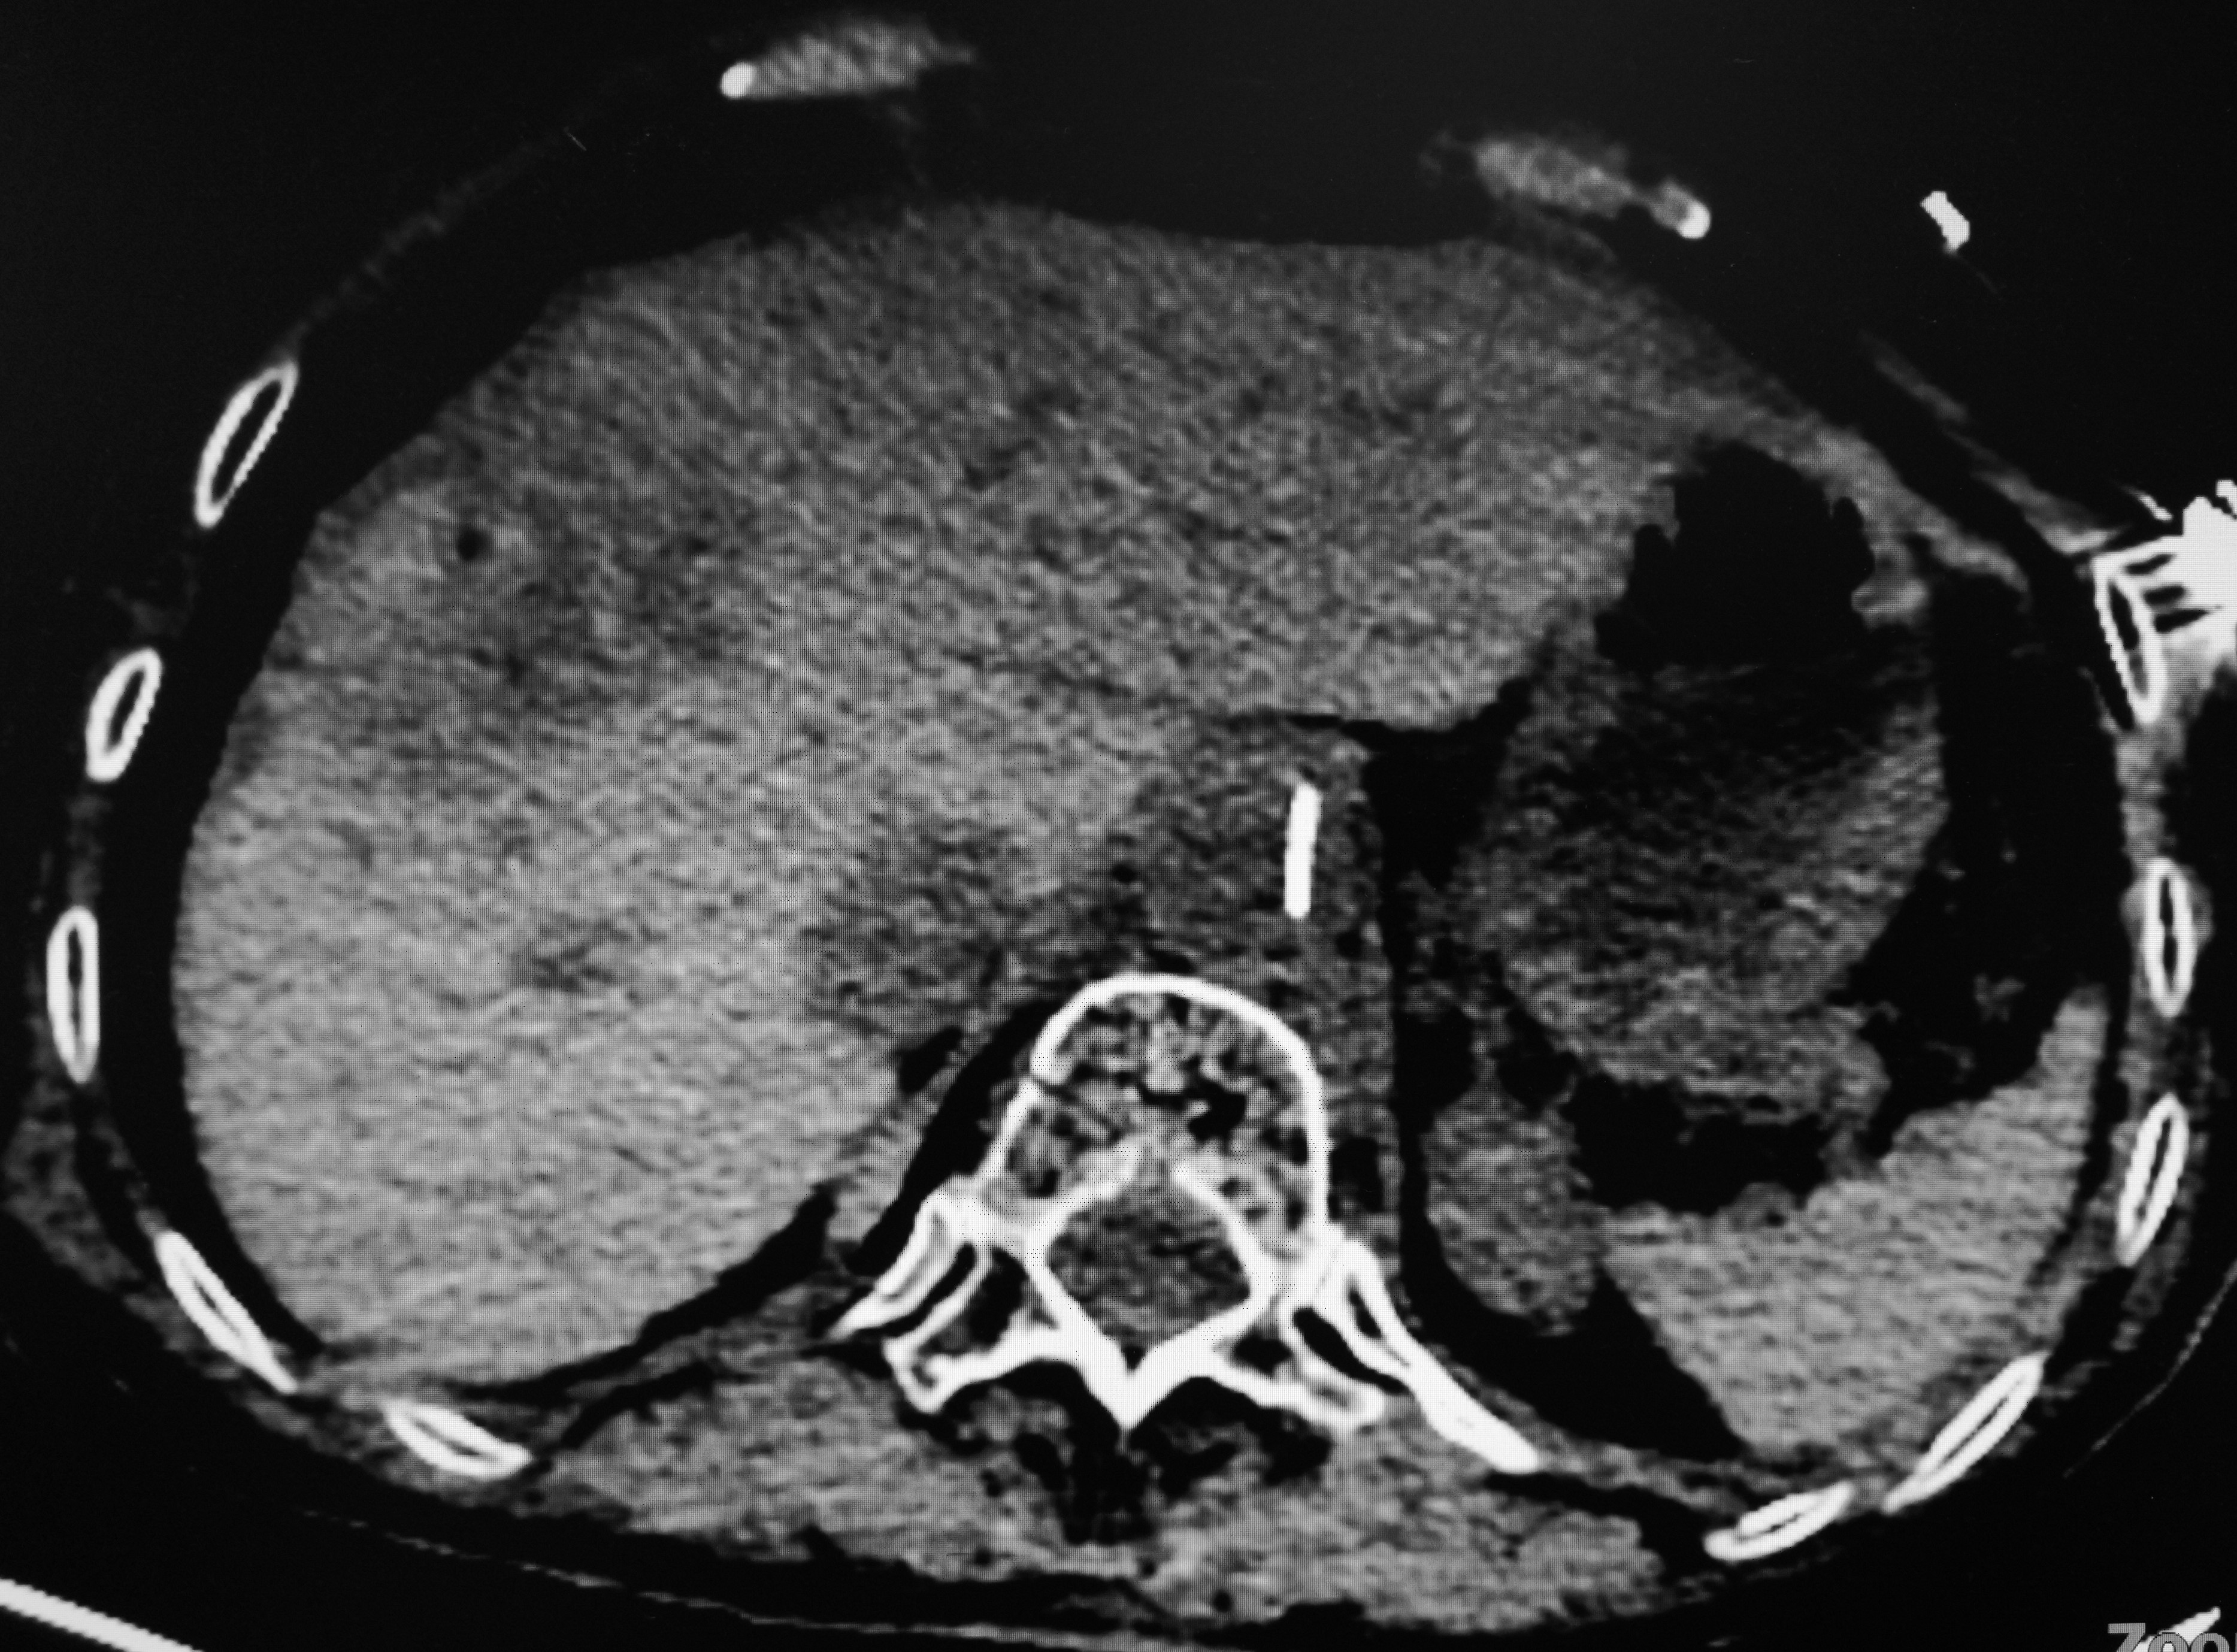

第五步:多角度多点消融结束后,拔针,CT扫描验证消融范围

消融前后CT对比:消融后肿瘤组织坏死